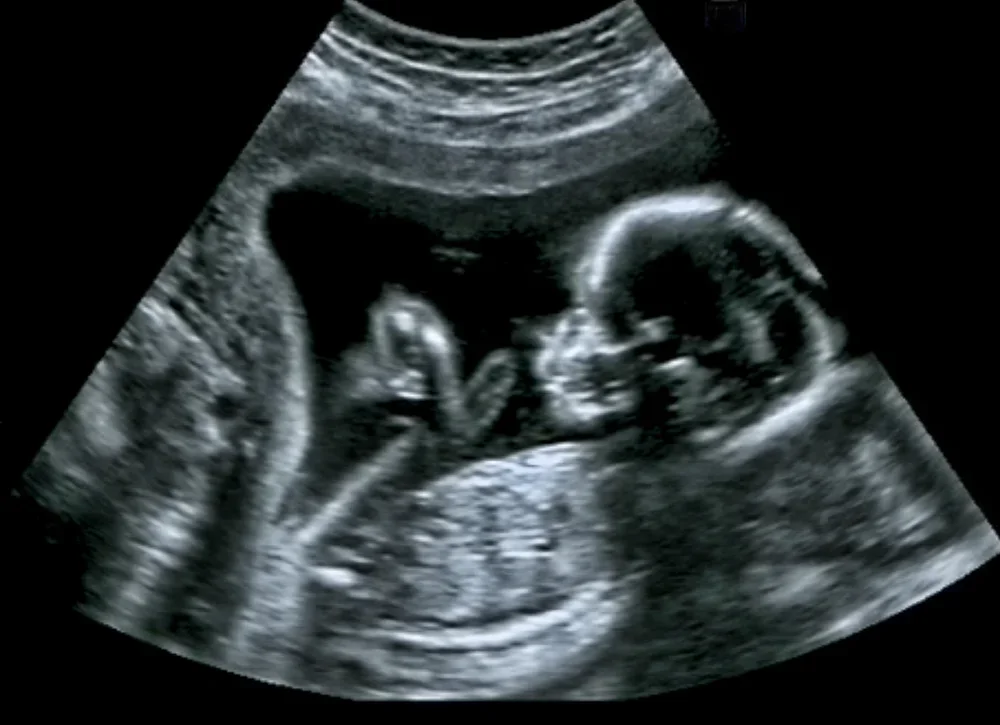

האם זה מסוכן להיבהל בהריון?

תקופת ההריון היא תקופה מרגשת ושמחה, ובמקביל, מלאה באתגרים רגישים. אישה בהריון עושה את המירב ואת הטוב ביותר מצידה על מנת לשמור על העובר שברחמה ולא לפגוע בהריון. ישנם גורמים רבים היכולים לפגוע בתקינות ההריון ואף לגרום להפלה של העובר חס ושלום, חלקם בשליטתנו והם נמנעים לחלוטין, וחלקם כלל לא תלויים במאמצים שנעשה עבור הצלחת ההריון.